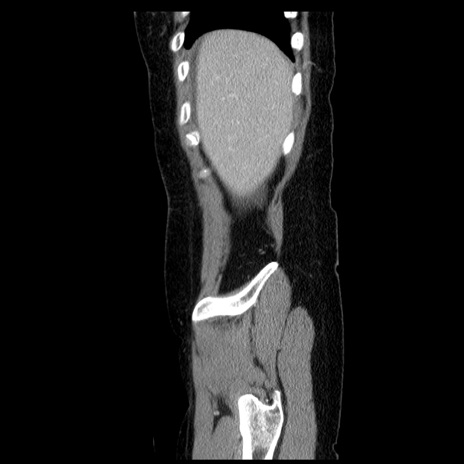

冠状断像

【症例】50歳代女性

【主訴】下腹部痛

【既往歴】卵巣癌術後(8年前に当院で卵巣摘出)

【身体所見】 意識清明、腹部:平坦、腸蠕動音→、やや硬、下腹部自発痛・圧痛あり、反跳痛あり、筋性防御なし。

【データ】WBC 16000、CRP 0.01